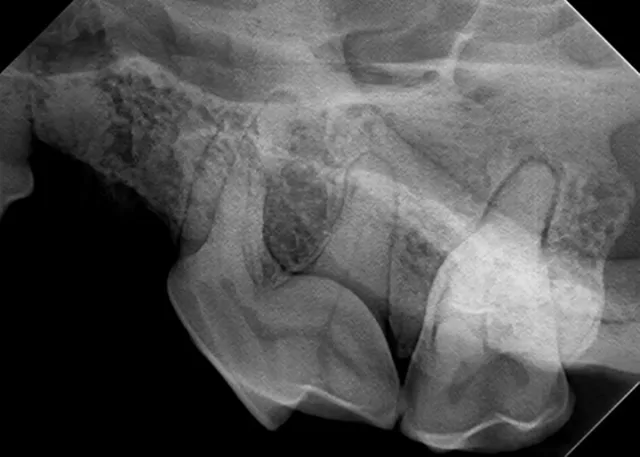

Sensor Placement

Place the sensor horizontally inside the oral cavity, with the cusp tip of the desired teeth at the edge of the sensor. Placing the sensor inside the oral cavity will provide enough room to catch the radiograph image.

Radiographs should be taken in the same order each time. Starting with the right maxillary molars, move the sensor and tube head around the entire arch until the left caudal maxilla is reached. Then, position the patient in ventral recumbency and repeat the process, starting with the left mandibular molars. Continue around the arch until the right caudal mandible is reached. This sequence is suggested because full-mouth-series templates included in most digital software programs are arranged in this order and will result in the mirror image for correct viewing of radiographs.